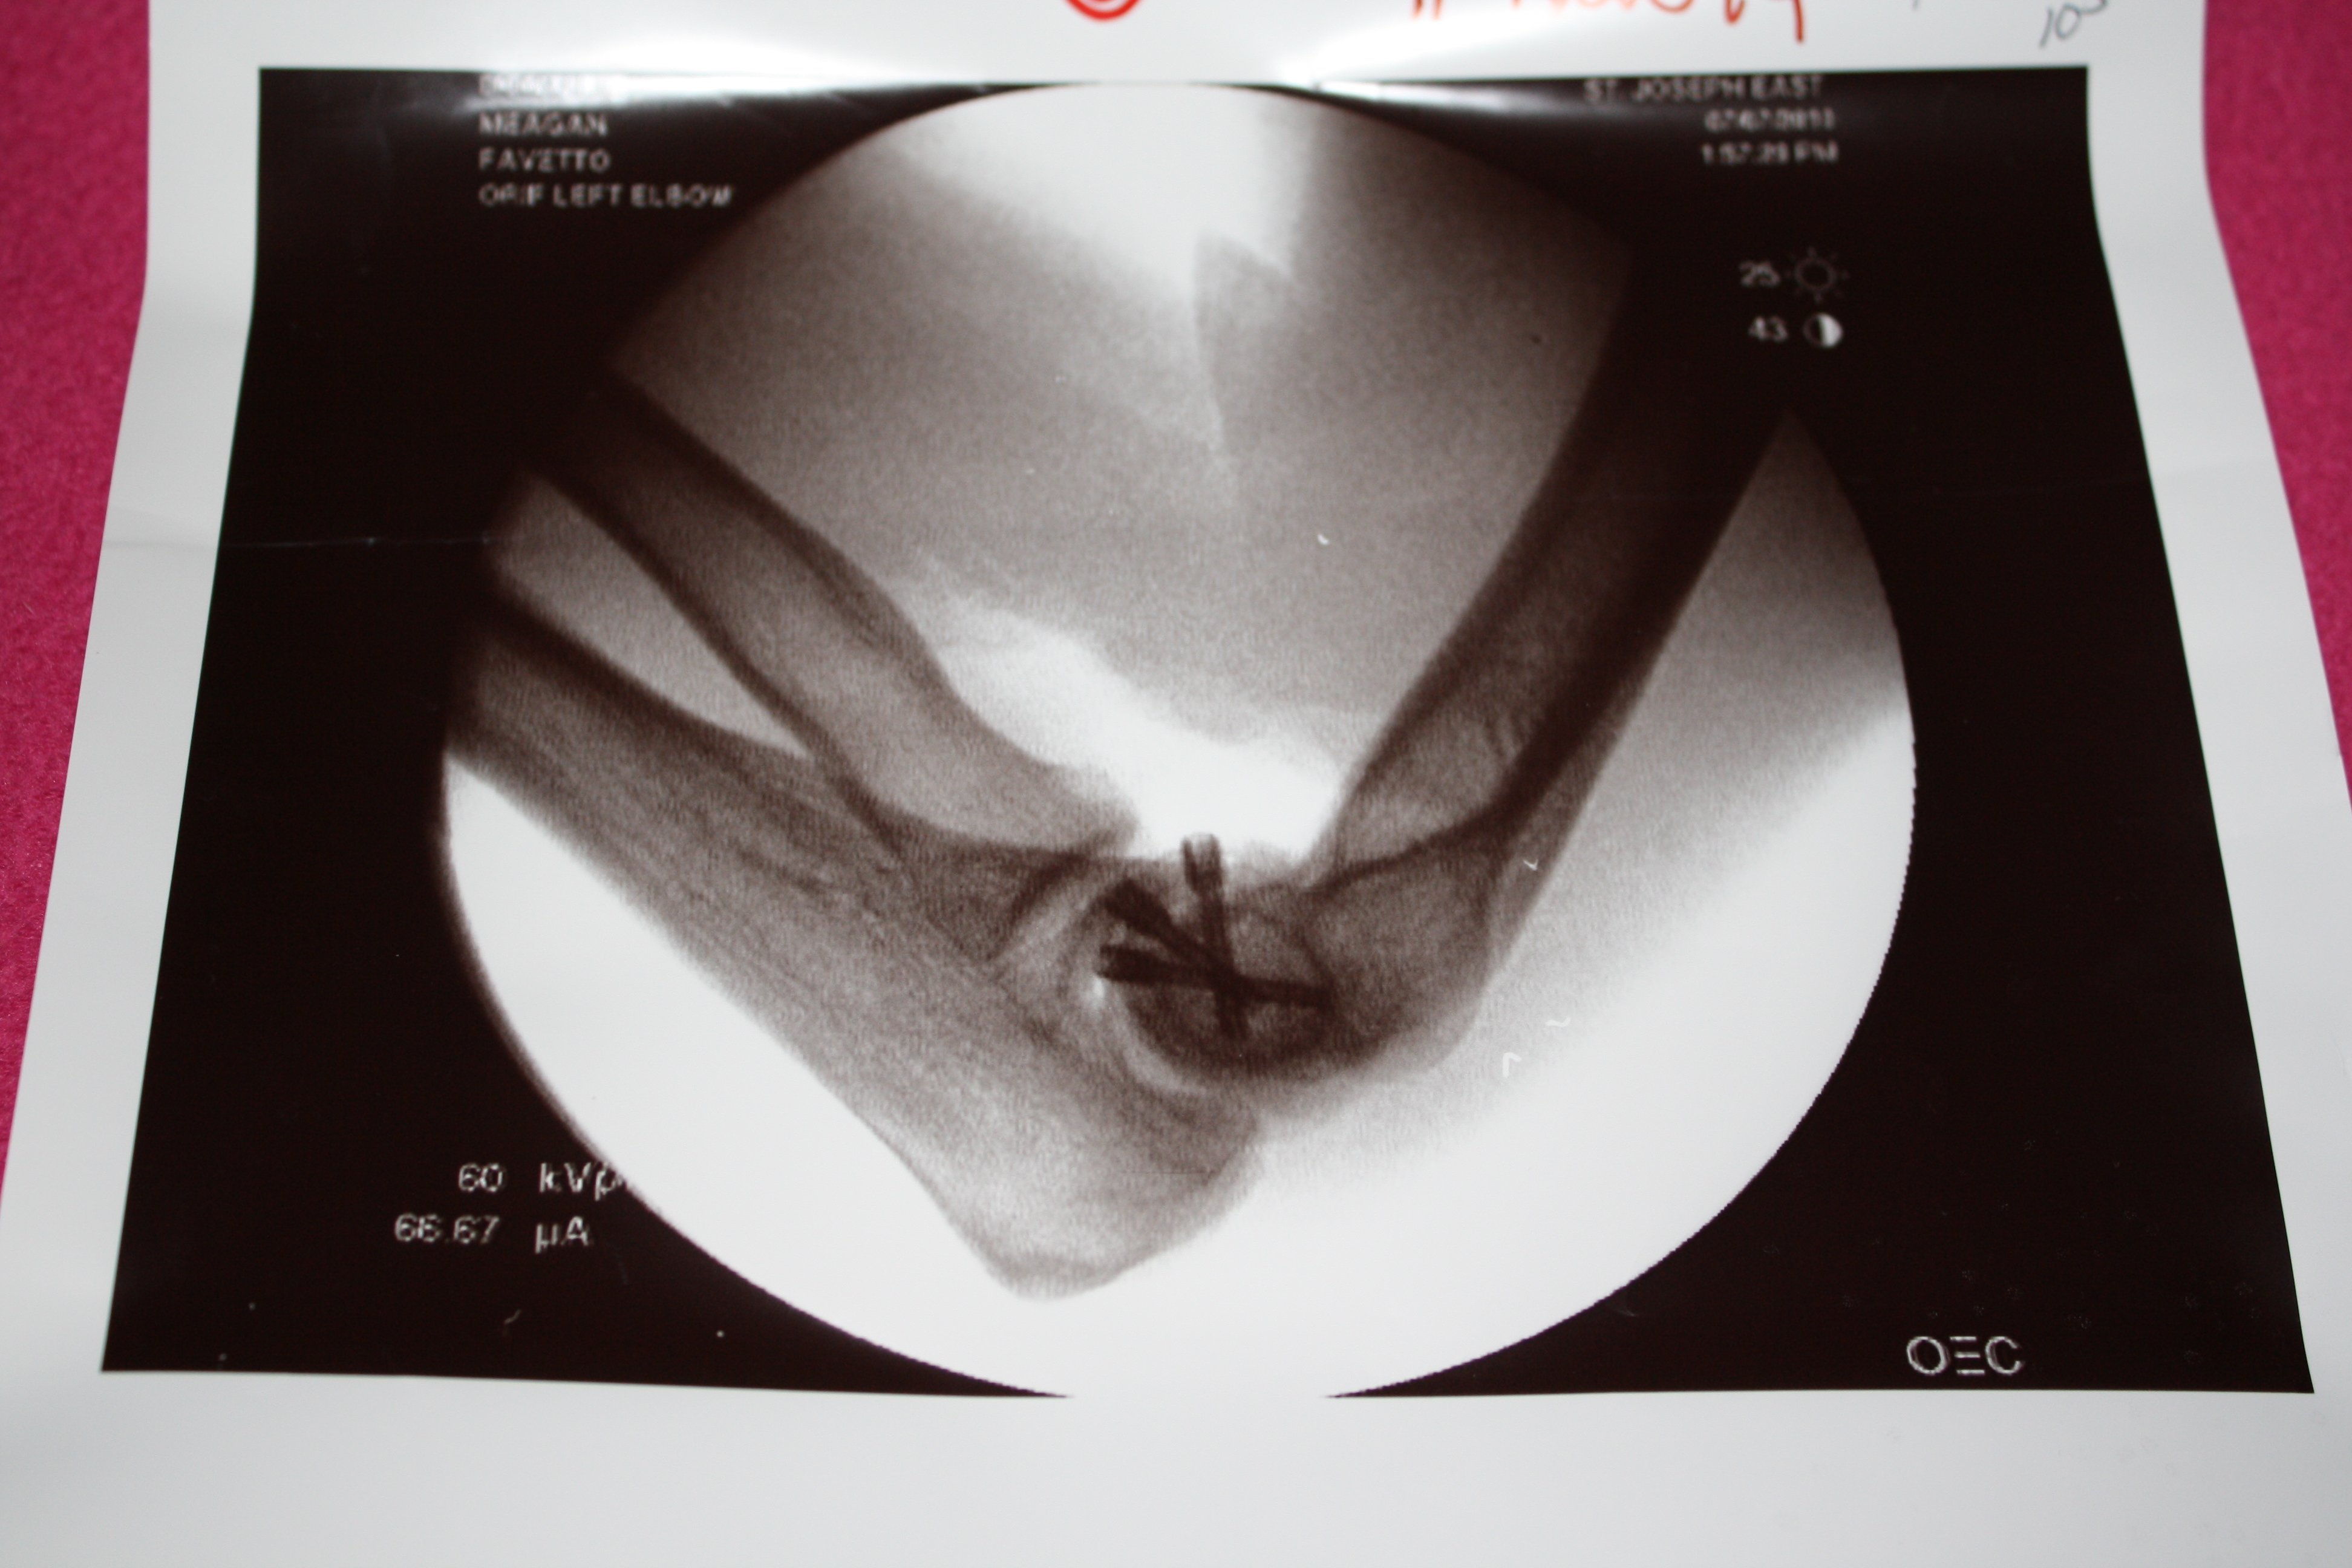

When I was 19 I was in an accident where I broke a bunch of stuff, including my back in six places, and took a good thump on the head (of which my mother is convinced I never recovered). I was in and out of the hospital/ICU for over a month. Reading her blog of course reminds me.